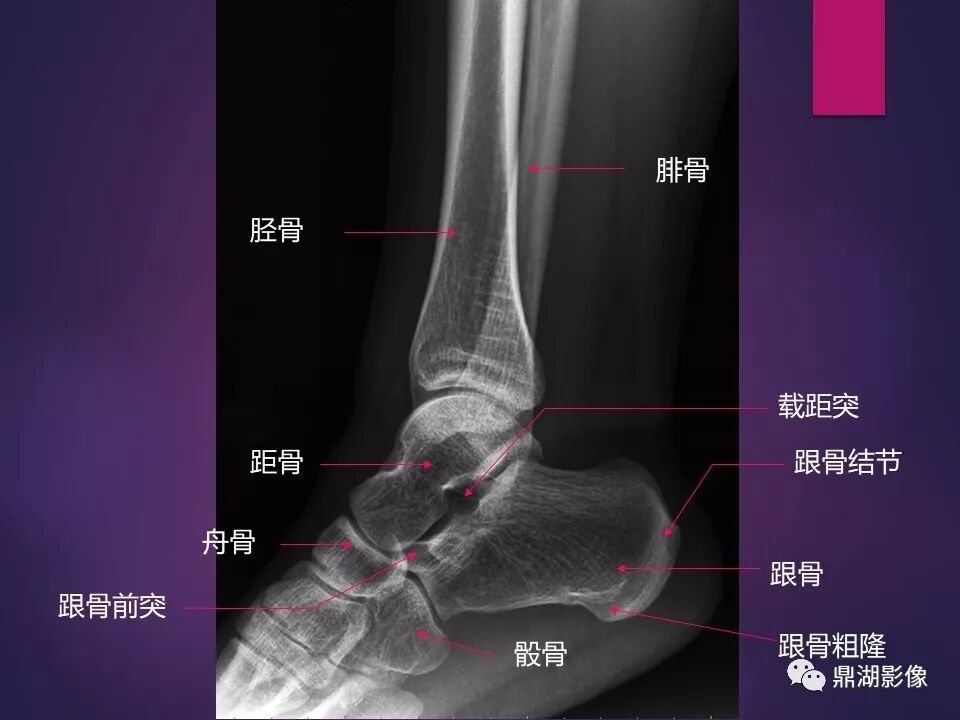

来源于:鼎湖影像 贵阳医学院医学影像系